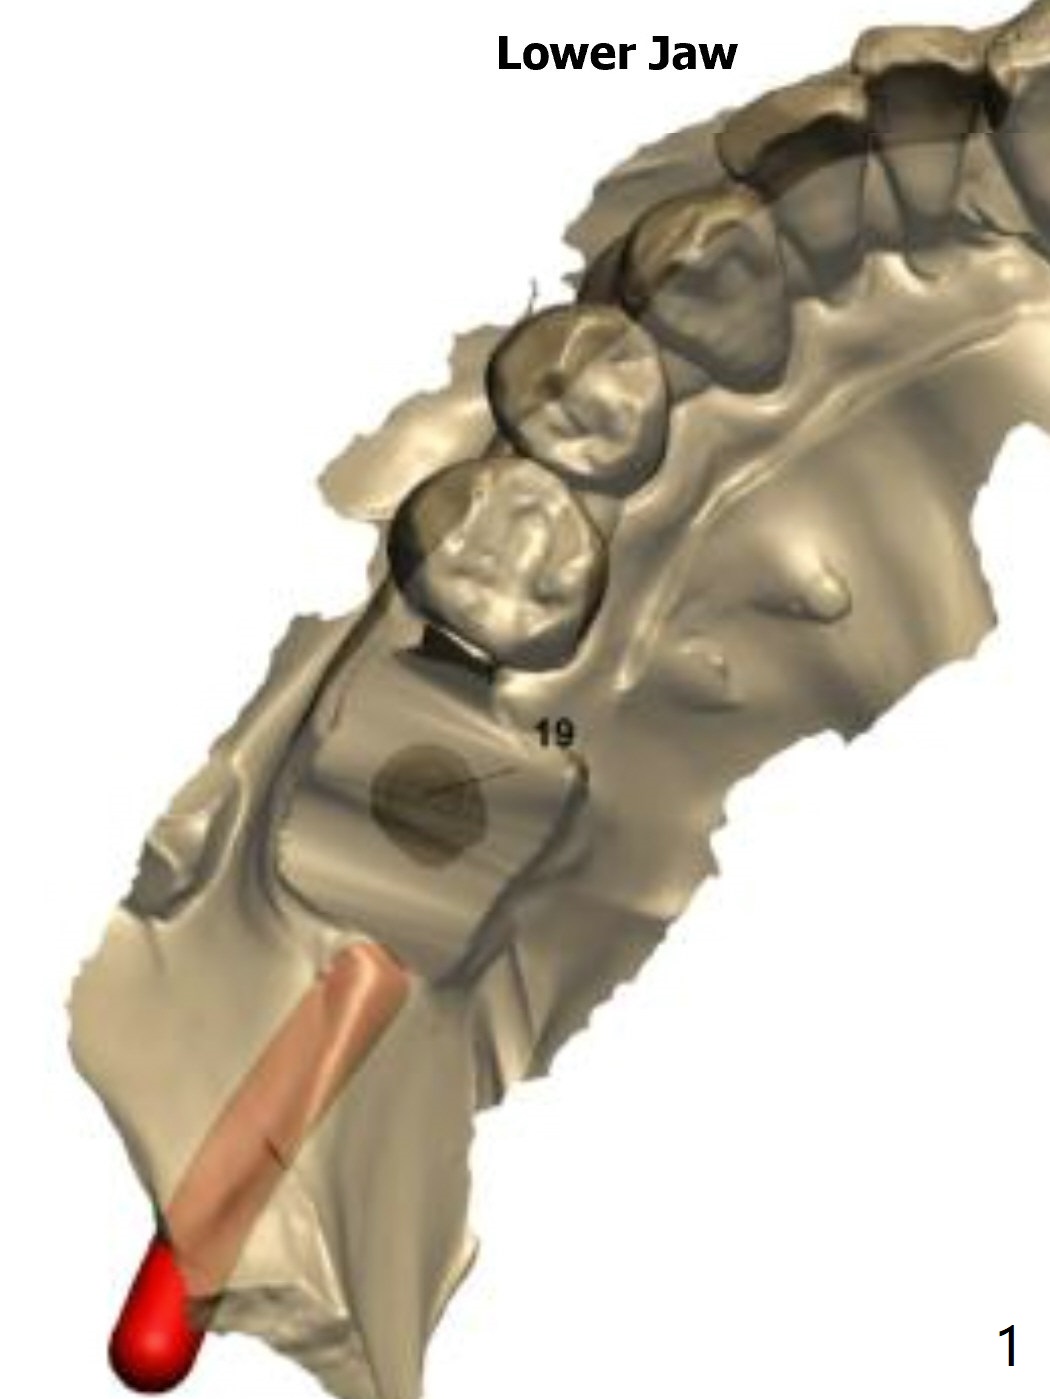

Lower Molar Immediate Implant, Trajectory Xin Wei, DDS, PhD, MS 1st edition 12/06/2018, last revision 12/13/2018